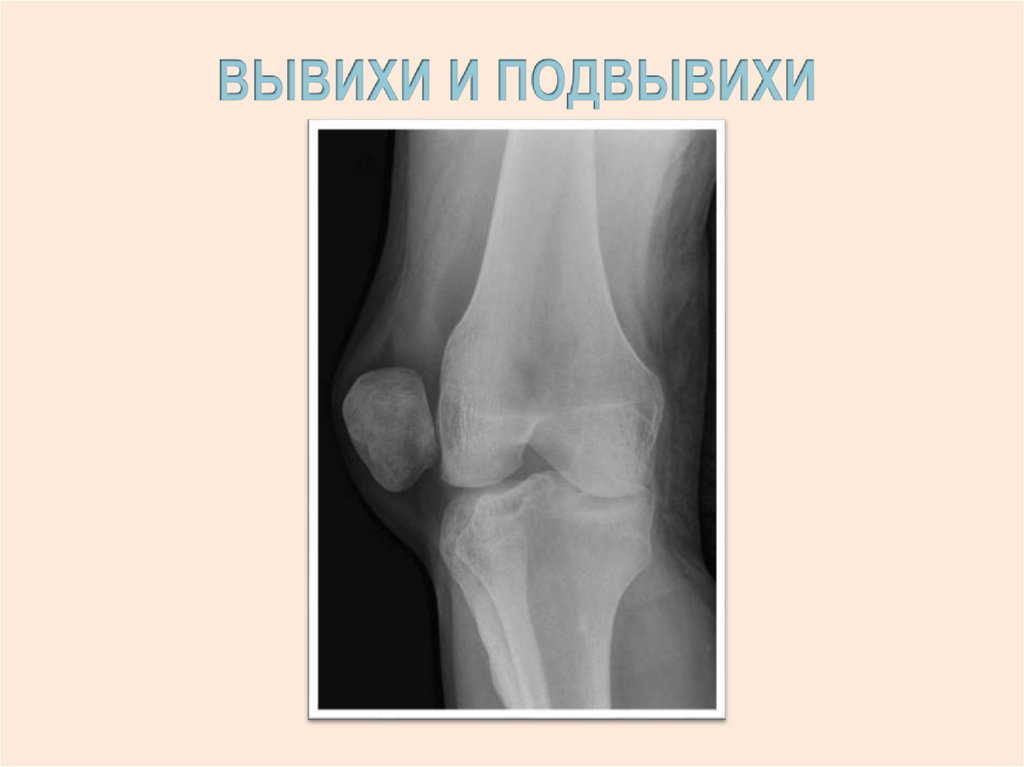

ВЫВИХ – ПОЛНОЕ нарушение

суставных соотношений

сочленяющихся костей

ПОДВЫВИХ – НЕПОЛНОЕ

нарушение суставных соотношений